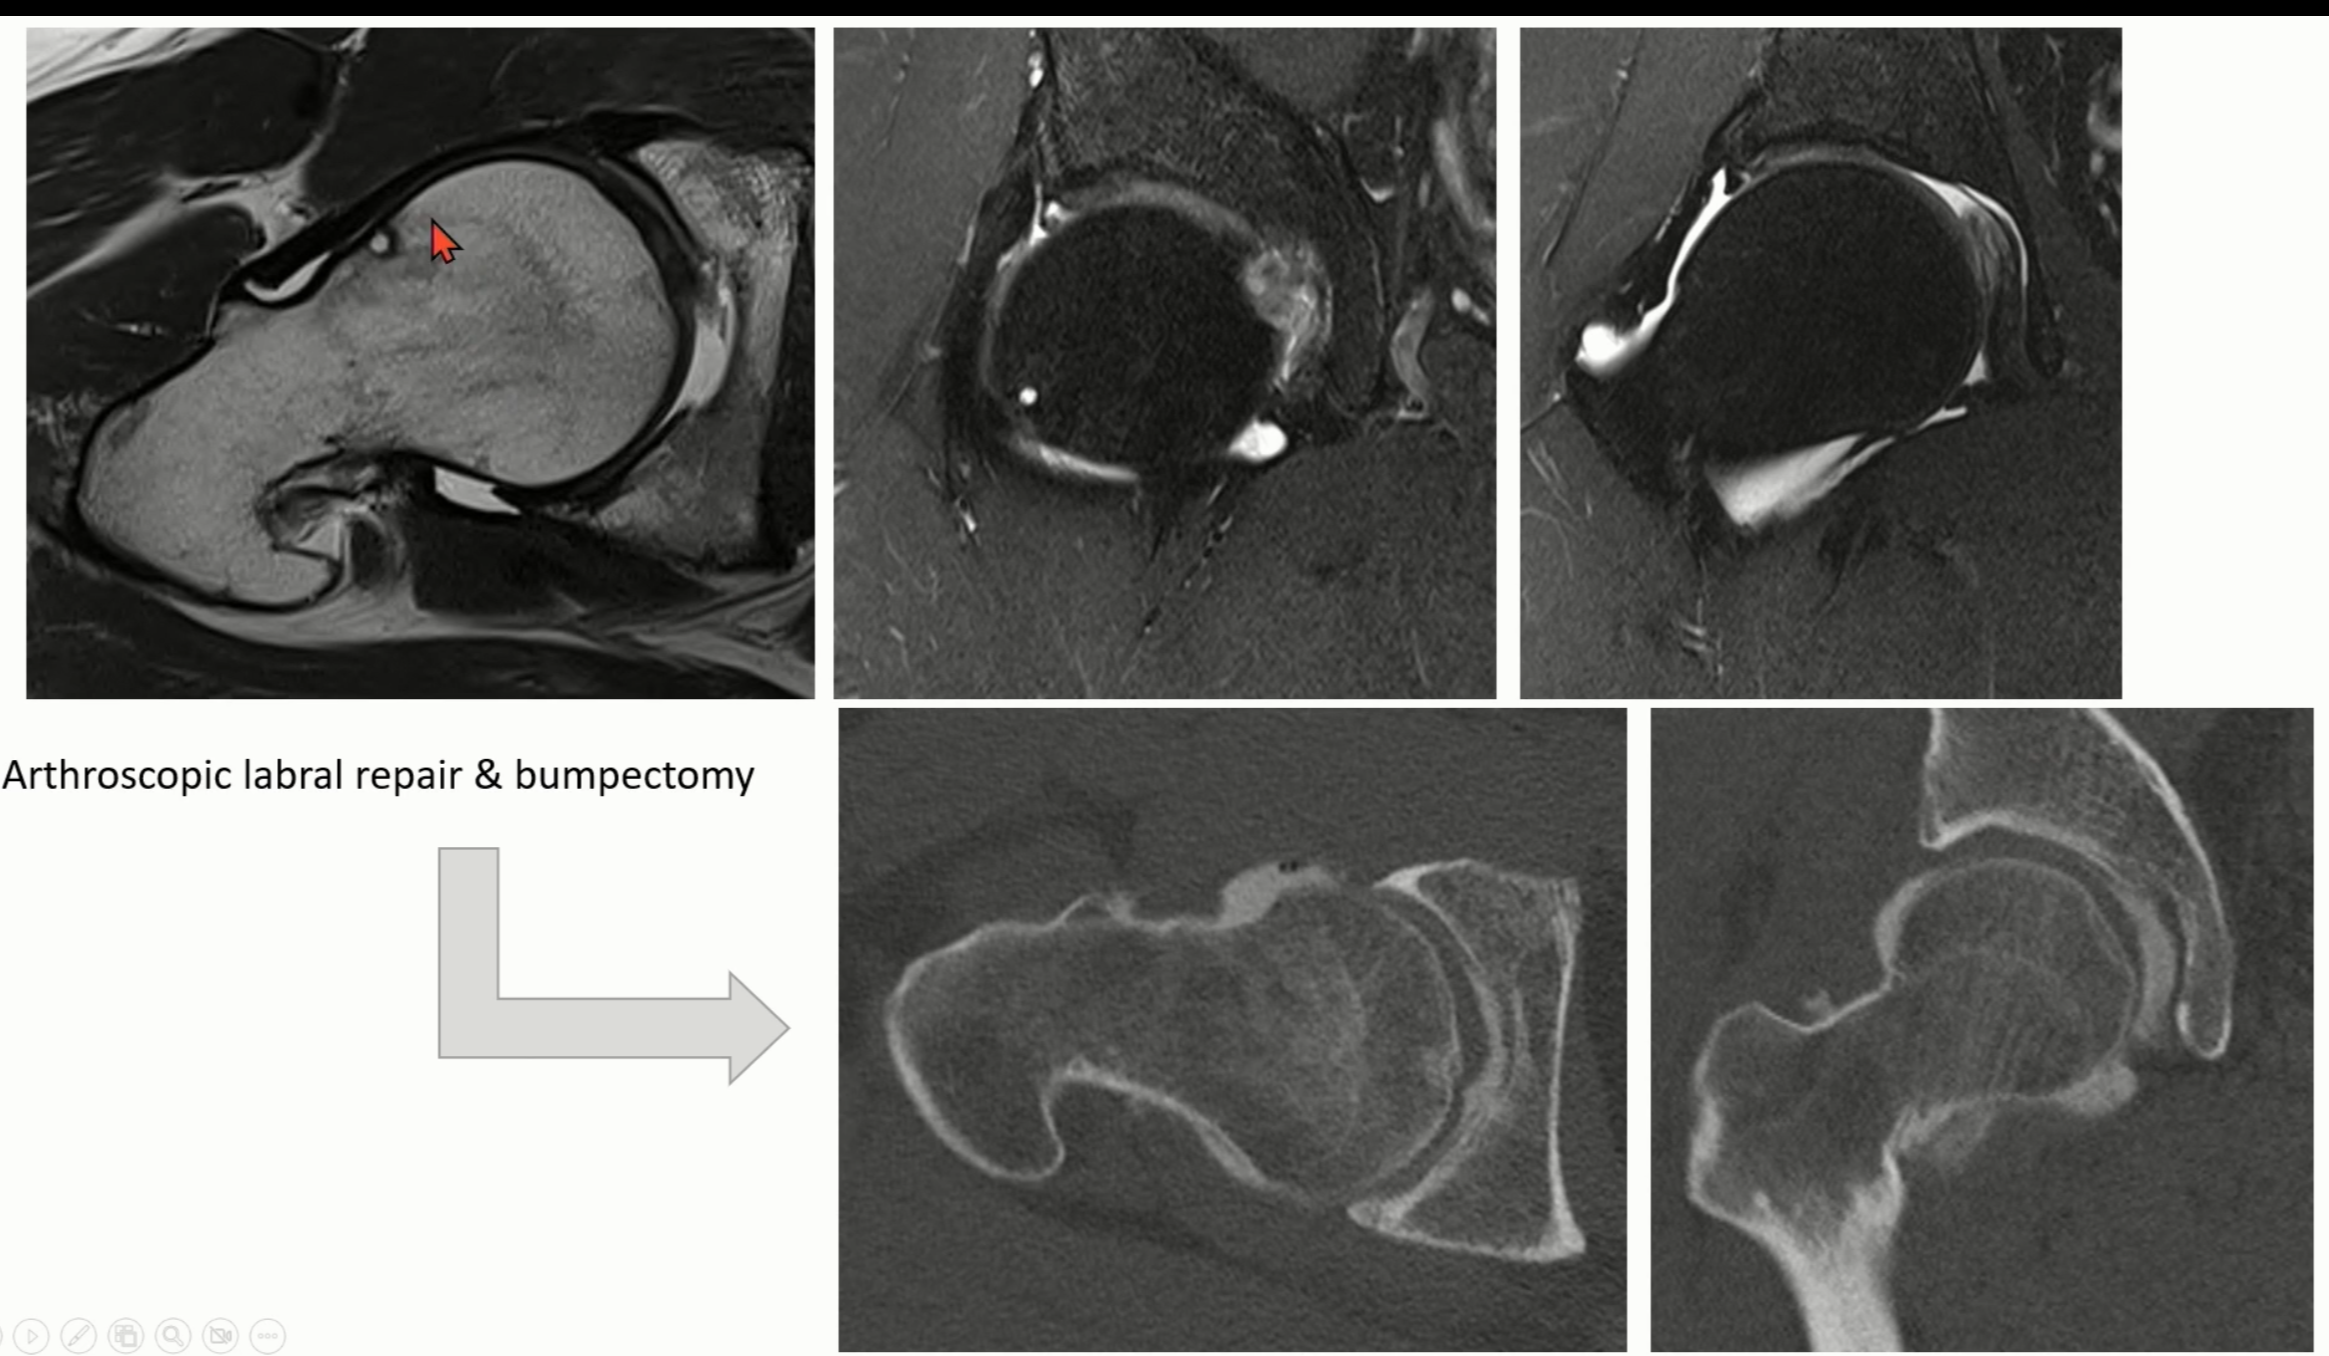

Axial 또는 modified dunn view에서 femur의 head와 neck의 사이에서 bump로 관찰됩니다.

(빨간 화살표)

CT나 MRI에서는 더 확실하게 볼 수 있습니다.

head/neck junction 부위에 cyst나 bump가 보이며, head의 구형이 소실된 모습을 볼 수 있습니다.

Case1)

Case 2)